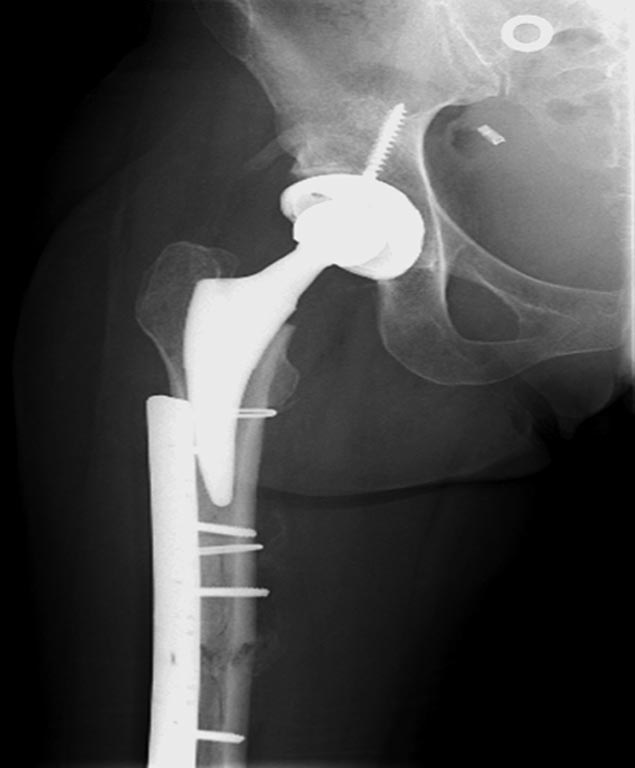

Здесь перечислены ортопедические повреждения: Rt. femoral shaft fracture, Rt femoral head fracture-dislocation, Rt distal femur fracture, Rt. open patella fracture, Rt. talus fracture dislocation, Rt. open humerus fracture, Left 5th metatarsal fracture, Left dislocation 1st TMT.

Интрамедуллярный остеосинтез бедра PFN Long

Фиксировать одним интрамедулярным гвоздем несколько переломов неплохая идея, но это не всегда удается. Для репозиции перелома шейки с вывихом головки (кстати, часть головки до сих пор остается внутри суставной впадины), потребуется много времени. Здесь каждый перелом требует особого подхода: например, для сохранения сферичности головки потребуется обширный доступ, а для остальных переломов различные трюки, что затрудняет фиксацию одним имплантатом!

При подборе фиксатора необходимо ориентироваться на следующие моменты: максимальный бенефит при минимальной инвазивности, создание стабильности при многоуровневом переломе, и наличие опыта работы с имплантатом. А предложенный фиксатор (PFN Long) не отвечает требованиям, потому что фиксатор предназначен для чрез-под вертельных и для высоких переломов бедра. Сомнения по поводу толстого (11 мм) болта в головку, хотя более пожилым с агрессивными конструкциями в головку проблем не бывает, а для молодых без надобности большие конструкции не рекомендуются. Лучше менее агрессивные, например, тонкие параллельные или перекрестные винты в проксимальном отделе гвоздя.

При лечении ипислатеральных переломов шейки и бедра лучший биомеханический эффект обеспечивают независимые друг от друга имплантаты, например, винты или DHS, и отдельная фиксация диафиза бедра. Можно интрамедуллярную фиксацию, но тогда, закрывая диафиз, мы отрезаем возможности фиксировать перелома шейки и головки!

Из вариантов фиксации для проксимального и диафиза бедра выбрали пластину, а по поводу артропластики остается вопрос между тотальным или геми.

На 25 день с момента травмы операция на Jackson table с боковым обширным доступом. Удаление стержней с местной обработкой. В тазобедренном суставе удаление головки, на дне вертлужной впадины полная отслойка хряща. Вертлужный компонент с одним винтом и короткая ножка - Fitmore press fit stem. На второй день однократно доза радиации для профилактики гетеретопической оссификации. Послеоперационный период без температуры. Выписана. Нагрузку разрешили на левой стороне, а полная в 3 мес. Здесь снимки при амбулаторном наблюдении: послеоперационно, 2 мес, 3 мес и 6 мес. Нагрузка полная, отсутствует хромота, и нет жалоб.